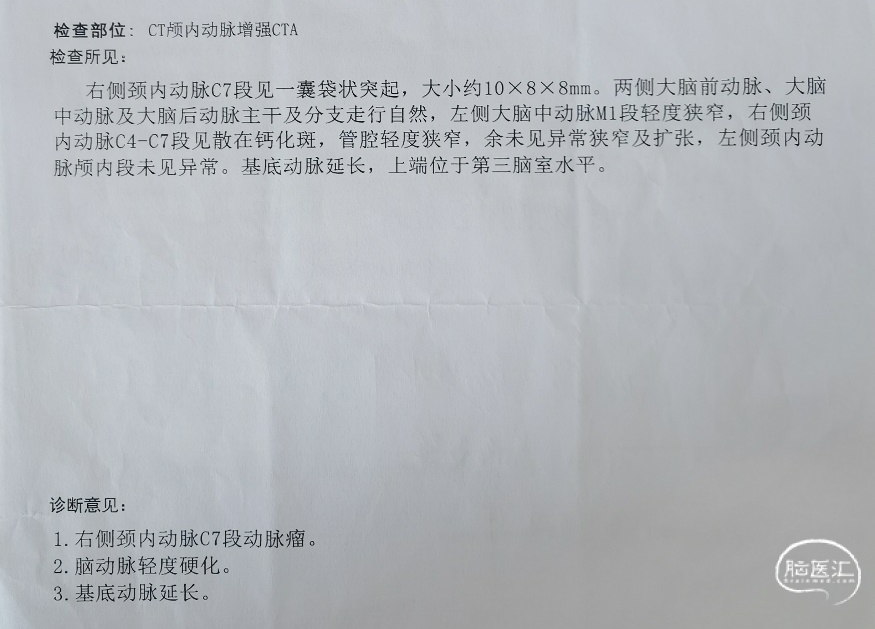

简要病史:患者近2周前体检行核磁MRI检查发现右侧颈内动脉动脉瘤,进一步完善头颅CTA检查明确为右侧颈内动脉C7段动脉瘤。

既往史:既往有高血压病史半年余,规律口服沙库巴曲缬沙坦控制。8年前曾行乳腺癌左侧乳房切除术。

入院查体情况:神志清楚,对答切题,四肢活动良好,GCS评分:15分,NIHSS评分0分,MRS评分:0分。

CTA:右侧颈内动脉C7段动脉瘤。

术前讨论:

老年女性患者,检查发现右侧颈内动脉C7段大动脉瘤,动脉瘤直径大于10mm,形态不规则,宽颈,手术指征明确,既往高血压、肿瘤病史,首选微创介入手术,术中造影证实动脉瘤直径大于10mm,绝对宽颈,形态不规则,局部仔瘤改变,右侧脉络膜前动脉从瘤体发出;微创介入血流导向装置是较优选择。